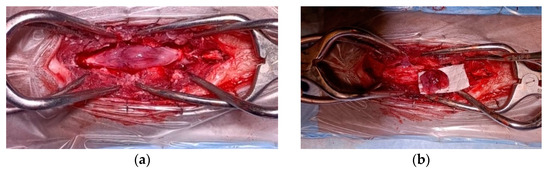

2. Case Description